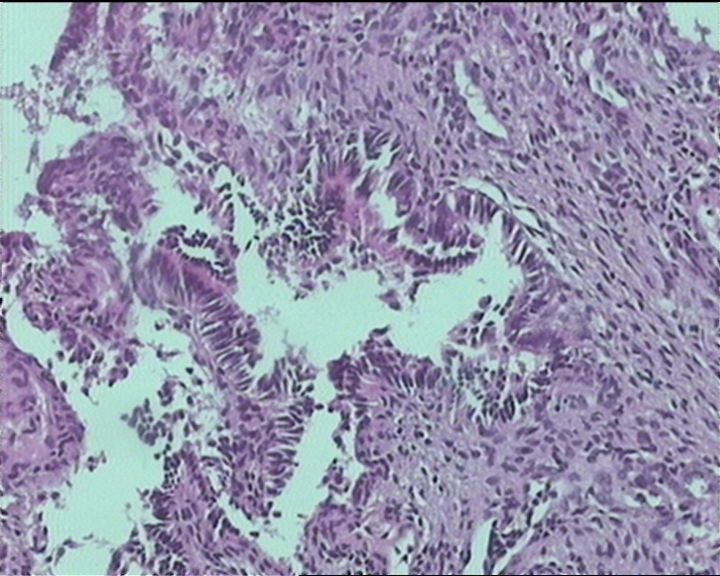

54岁女性,临床“宫颈息肉”送检;巨检:组织一块1。5*1CM,灰红。

输卵管粘膜化生

It is benign. Benign endocervical polyp with tubal metaplasia.

细胞及腺体均有异形,图6、11、16象有纤维间质反应,考虑高级别上皮内瘤变/原位癌,腺癌不能除外。

Sternberg病理学上诊断宫颈原位腺癌的标准是腺体的上皮去粘液分化,呈乳头状或筛网状增生,核分裂易见,这例显然达不到此标准。此例还是归入到腺上皮不典型增生为好。

杨老师说它是良性的,是个颈管内膜息肉伴输卵管上皮化生,良性